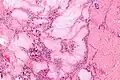

A tophus (Latin: "stone", pl.: tophi) is a deposit of monosodium urate crystals, in people with longstanding high levels of uric acid (urate) in the blood, a condition known as hyperuricemia. Tophi are pathognomonic for the disease gout. Most people with tophi have had previous attacks of acute arthritis, eventually leading to the formation of tophi. Chronic tophaceous gout is known as Harrison Syndrome.[1]

Tophi form in the joints, cartilage, bones, and other places throughout the body. Sometimes, tophi break through the skin and appear as white or yellowish-white, chalky nodules. Without treatment, tophi may develop on average about ten years after the onset of gout, although their first appearance can range from three to forty-two years. The development of gouty tophi can also limit joint function and cause bone destruction, leading to noticeable disabilities, especially when gout cannot successfully be treated.[2]

It appears that monosodium urate crystals trigger a distinct physiological NETosis pathway that coats them in DNA. These coated crystals then persist in tissues as a foreign body granuloma constituting gouty tophus.[4]